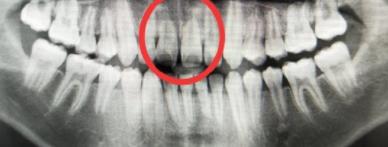

孩子門牙受外傷(shang) 後牙根變短了

牙齒外傷(shang) 通常需要及時到醫院拍片檢查牙齒情況,確定是否傷(shang) 及神經,以及是否需要做鬆牙固定等處理,還需要確定牙槽骨的等情況。

牙根折斷